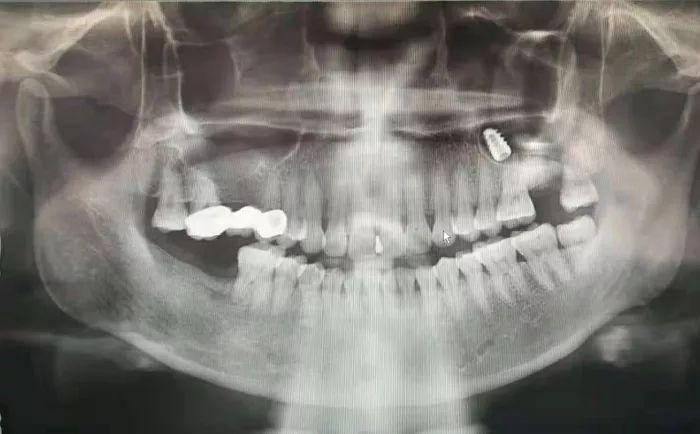

該科副主任崔婧正準(zhǔn)備下班,見(jiàn)狀又忙穿上了白大袿到診室為李先生(化名)進(jìn)行詳細(xì)檢查,影像科馬玉新和陳齊齊醫(yī)生為其拍攝了口腔曲面斷層片發(fā)現(xiàn)其左側(cè)上頜竇內(nèi)有一枚疑似金屬的高密度影像。崔婧仔細(xì)詢問(wèn)病史后得知,李先生于當(dāng)?shù)啬吃\所做上頜牙齒種植術(shù),卻不慎將種植體捅入了上頜竇,雖然去了多家醫(yī)院卻始終沒(méi)能得到有處理。崔婧憑借嫻熟的技術(shù)在局麻下對(duì)患者進(jìn)行上頜竇開(kāi)窗術(shù),醫(yī)護(hù)人員密切配合,順利取出了上頜竇內(nèi)的種植體。李先生對(duì)醫(yī)務(wù)人員的耐心和的技術(shù)以及拖班后又井然有序的完成急診處理工作表示由衷的感謝。